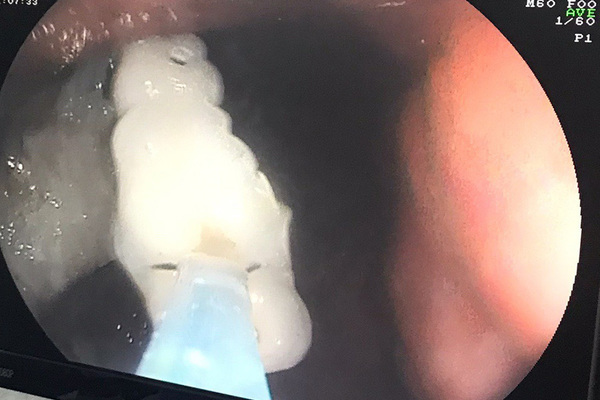

| Hình ảnh hàm răng giả nằm trong phế quản bệnh nhân |

Tại bệnh viện, bác sĩ hội chẩn và chỉ định nội soi phế quản để lấy dị vật cho bệnh nhân. Sau 30 phút, ê-kíp lấy thành công dị vật là 4 răng giả móc ngay phế quản của bệnh nhân.